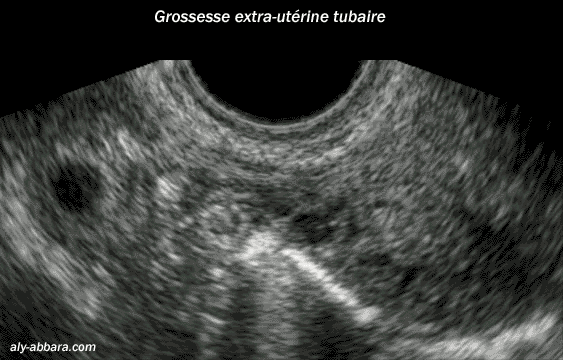

L'aspect échographique

d'une grossesse extra-utérine tubaire située dans la portion moyenne

de la trompe ; non rompue.

Sur cette image on peut voir le sac gestationnel

avec sa couronne trophoblastiqe et sa vésicule

ombilicale ; elle est implantée dans la trompe avec cavité utérine vide

de toute trace de grossesse.